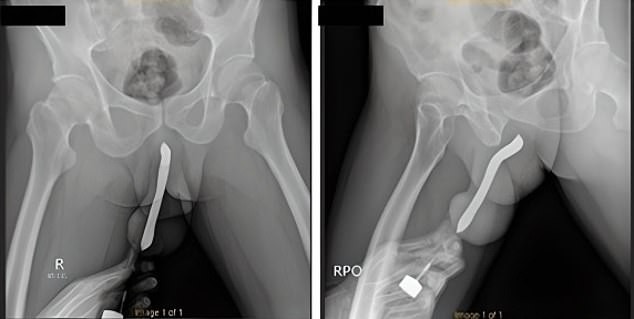

Eye-watering injury of Indonesian man, 43, who shoved a toothbrush into his penis which snapped during sex

- The unnamed 43-year-old waited 12 hours before seeking medical attention

- The man confessed to using the toothbrush for his own 'sexual satisfaction'